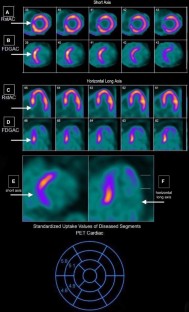

F18-FDG PET/CT with MPI was used in CS diagnosis (N = 67). Mean and max SUV were measured and grouped as basal, mid, and apical disease. Post-scan ventricular tachycardia, AICD placement, complete heart block, pacemaker placement, atrial fibrillation, heart failure, and cardiac-related hospital admissions were recorded (mean follow up 2.98 ± 2 years). Poisson regression analysis revealed that max SUV, mean SUV, as well as mean basal SUV, and LVEF were significantly associated with total cardiac events. Max SUV odds ratio (OR) = 1.068 (95% CI 1.024-1.114, P = 0.002), mean SUV OR = 1.059 (95% CI 1.008-1.113, P = 0.023), mean SUV OR = 1.061 (95% CI 1.012-1.112, P = 0.014), scan LVEF OR = 0.731 (95% CI 0.664-0.805, P < 0.001).

SUV at time of CS diagnosis has significant associations with future cardiac events. Patients with higher SUV, particularly in basal segments, are at increased risk of events. Further studies are needed to identify treatment methods utilizing risk stratification of CS.

Figure 1